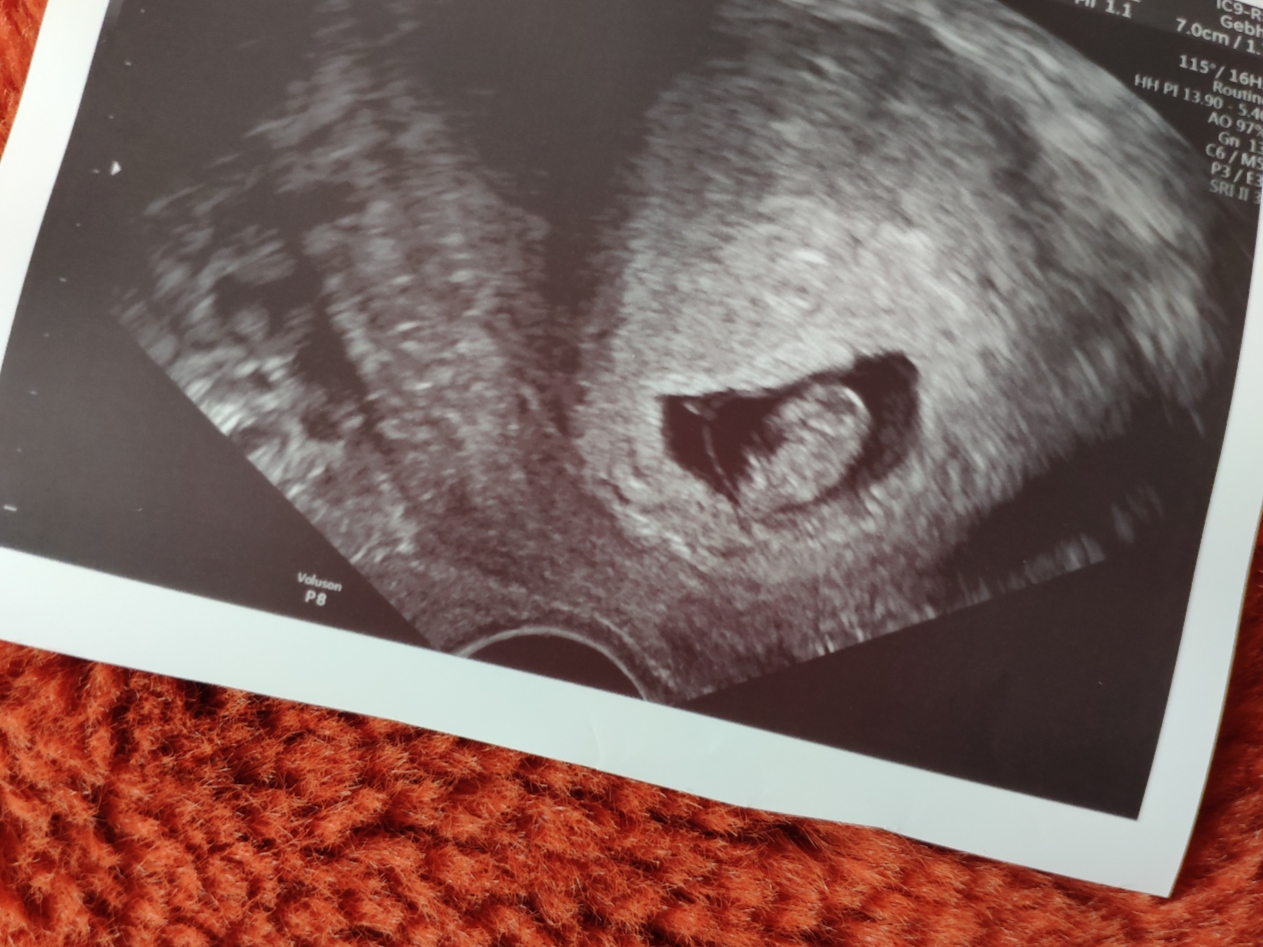

Ruhe ist ab jetzt angesagt. Nochmal will ich kein Blut im Schlüppi sehen. Aber wir wissen ja, woher es kam, nicht wahr? 🤭

Noch ein Hämatom werde ich jedenfalls nicht provozieren. Radieschen soll wachsen, alles andere ist nicht so wichtig.